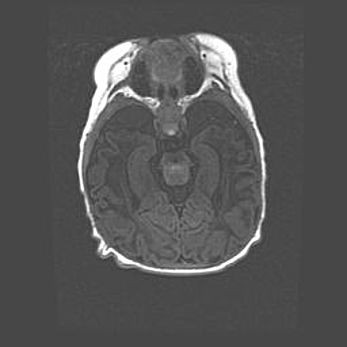

Множественные кисты обоих полушарий головного мозга, наибольшая из них в правой затылочной области. Ассиметричная атрофическая гидроцефалия.

Возраст: 7 месяцев

Вес: 5660 г

Пол: мужской

Окружность головы: 41,5 см

Срок гестации: 28-29 недель

Кисты головного мозга развиваются в результате многоочаговых некрозов вещества мозга и возникают вследствие перенесенной перинатальной инфекции, менингитов, энцефалитов, асфиксии, родовой травмы, расстройств мозгового кровообращения различного генеза. Образованию кист в веществе головного мозга плодов и новорожденных способствуют такие факторы, как высокое содержание в нем воды, недостаточная (или отсутствие) миелинизация и слабая астроглиальная реакция на повреждение.

Кисты могут сочетаться с гидроцефалией и другими поражениями головного мозга.